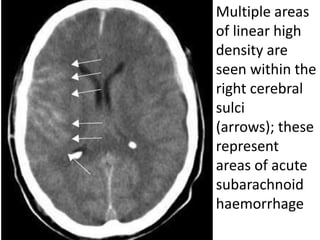

Multiple areas

of linear high

density are

seen within the

right cerebral

sulci

(arrows); these

represent

areas of acute

subarachnoid

haemorrhage

Subarachnoid Hemorrhage

Subarachnoid haemorrhage

Radiological features

● Non-contrast CT is sensitive within 4–5

hours of onset.

● Look for acute haemorrhage (increased

density) in the cortical sulci, basal

cisterns, Sylvian fissures, superior

cerebellar cisterns and in the ventricles.

Multiple areas of linearhigh density are seen within the right cerebral sulci (arrows); these represent areas of acute subarachnoid haemorrhage